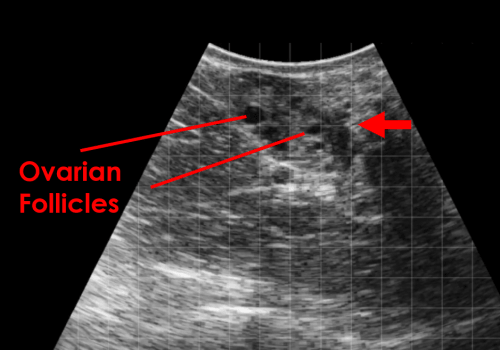

Follicles

This image shows multiple small ovarian follicles. The fluid filled follicles appear anechoic (black) and are surrounded by the stroma of the ovary (red arrow).